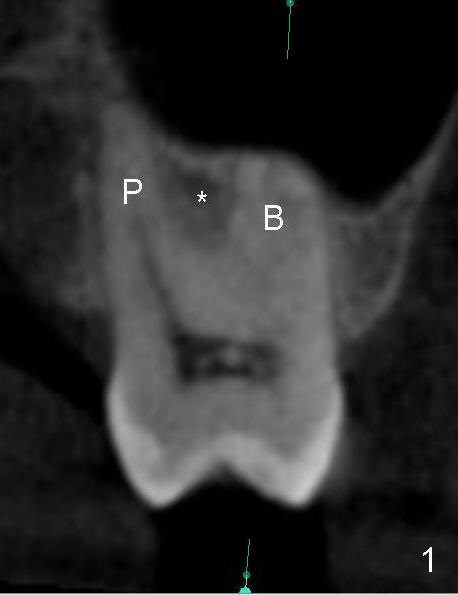

When the buccal roots are fused, there are 3 potential sites for immediate implant (Fig.1'): septum (*), buccal (B) and palatal (P) sockets. Septal placement (6.9x8 mm bone level implant) is the most ideal for restoration (Fig.3). The length of the implant can be increased (10 mm) with sinus lift so that the base of the implant between the buccal and palatal apices in height (Fig.4). Primary stability is derived mainly from the implant body engagement into the septum (Fig.5 coronal section through the septum). If bone density in the septum is high, a small implant may be appropriate (Fig.6,7: 6.4x8 mm). The large implant (6.9 mm) is chosen so that amount of bone graft to be used (Fig.8 red circles) is less.